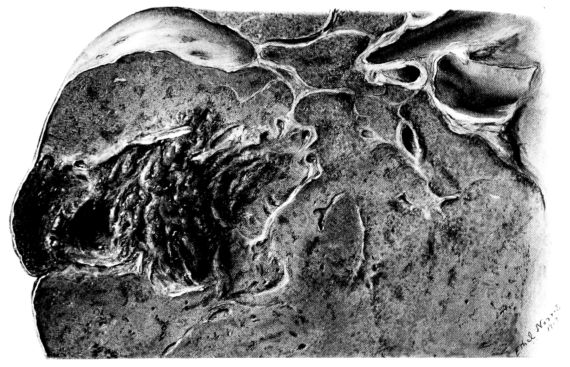

FIG. III. AUTOPSY NO. 90. DRAWING FROM A LESION OF THE TRACHEA (SOMEWHAT OLDER THAN THAT ILLUSTRATED IN FIGURE II). THE MUCOSA IS ENTIRELY LACKING. CONGESTION AND EDEMA ARE THE STRIKING FEATURES IN THE SUBMUCOSA. THE NECROTIZING PROCESS HAS EXTENDED INTO THE MUCUS GLANDS. THIS IS SHOWN IN THE LOWER PICTURE.

The changes are less marked, perhaps, in the trachea than in its finer ramifications. The mucosa is constantly more or less destroyed and large areas, usually focal, are entirely devoid of their epithelial covering. This is replaced by a sparse exudate, composed largely of red blood cells, mucus, a small amount of fibrin, and nuclear fragments (Fig. II). It may dip into the submucosa for a short distance, but usually these indentures are associated with the ducts of the mucous glands into which the inflammatory reaction extends. A more striking feature than the exudate, however, is the edema and the congestion of the submucosa. The loose areolar tissue of the submucosa is spread widely apart, and throughout it distended blood vessels are very conspicuous. Occasionally such a vessel is broken and actual hemorrhage appears in the submucosa. Occasionally, too, the inflammation extends down the duct to the mucous gland itself, and here, also, aplastic inflammatory reaction is evident, inasmuch as the acini now stain intensely red with the cells undifferentiated from each other and specked here and there by broken remains of the dead nuclei (Fig. III). After the disease has continued for a short period, even at the end of five or six days, some regeneration of the epithelial lining may be seen (3) (Fig. IV). But despite this, the acute picture persists, and there goes on, side by side, an attempted repair characterized by epithelial regeneration and the same evidence of acute change. Since the lesion is essentially a superficial one, scars or contractures of any extent are not encountered in the trachea, even in examples of the disease that have ended fatally only after many weeks.[4]